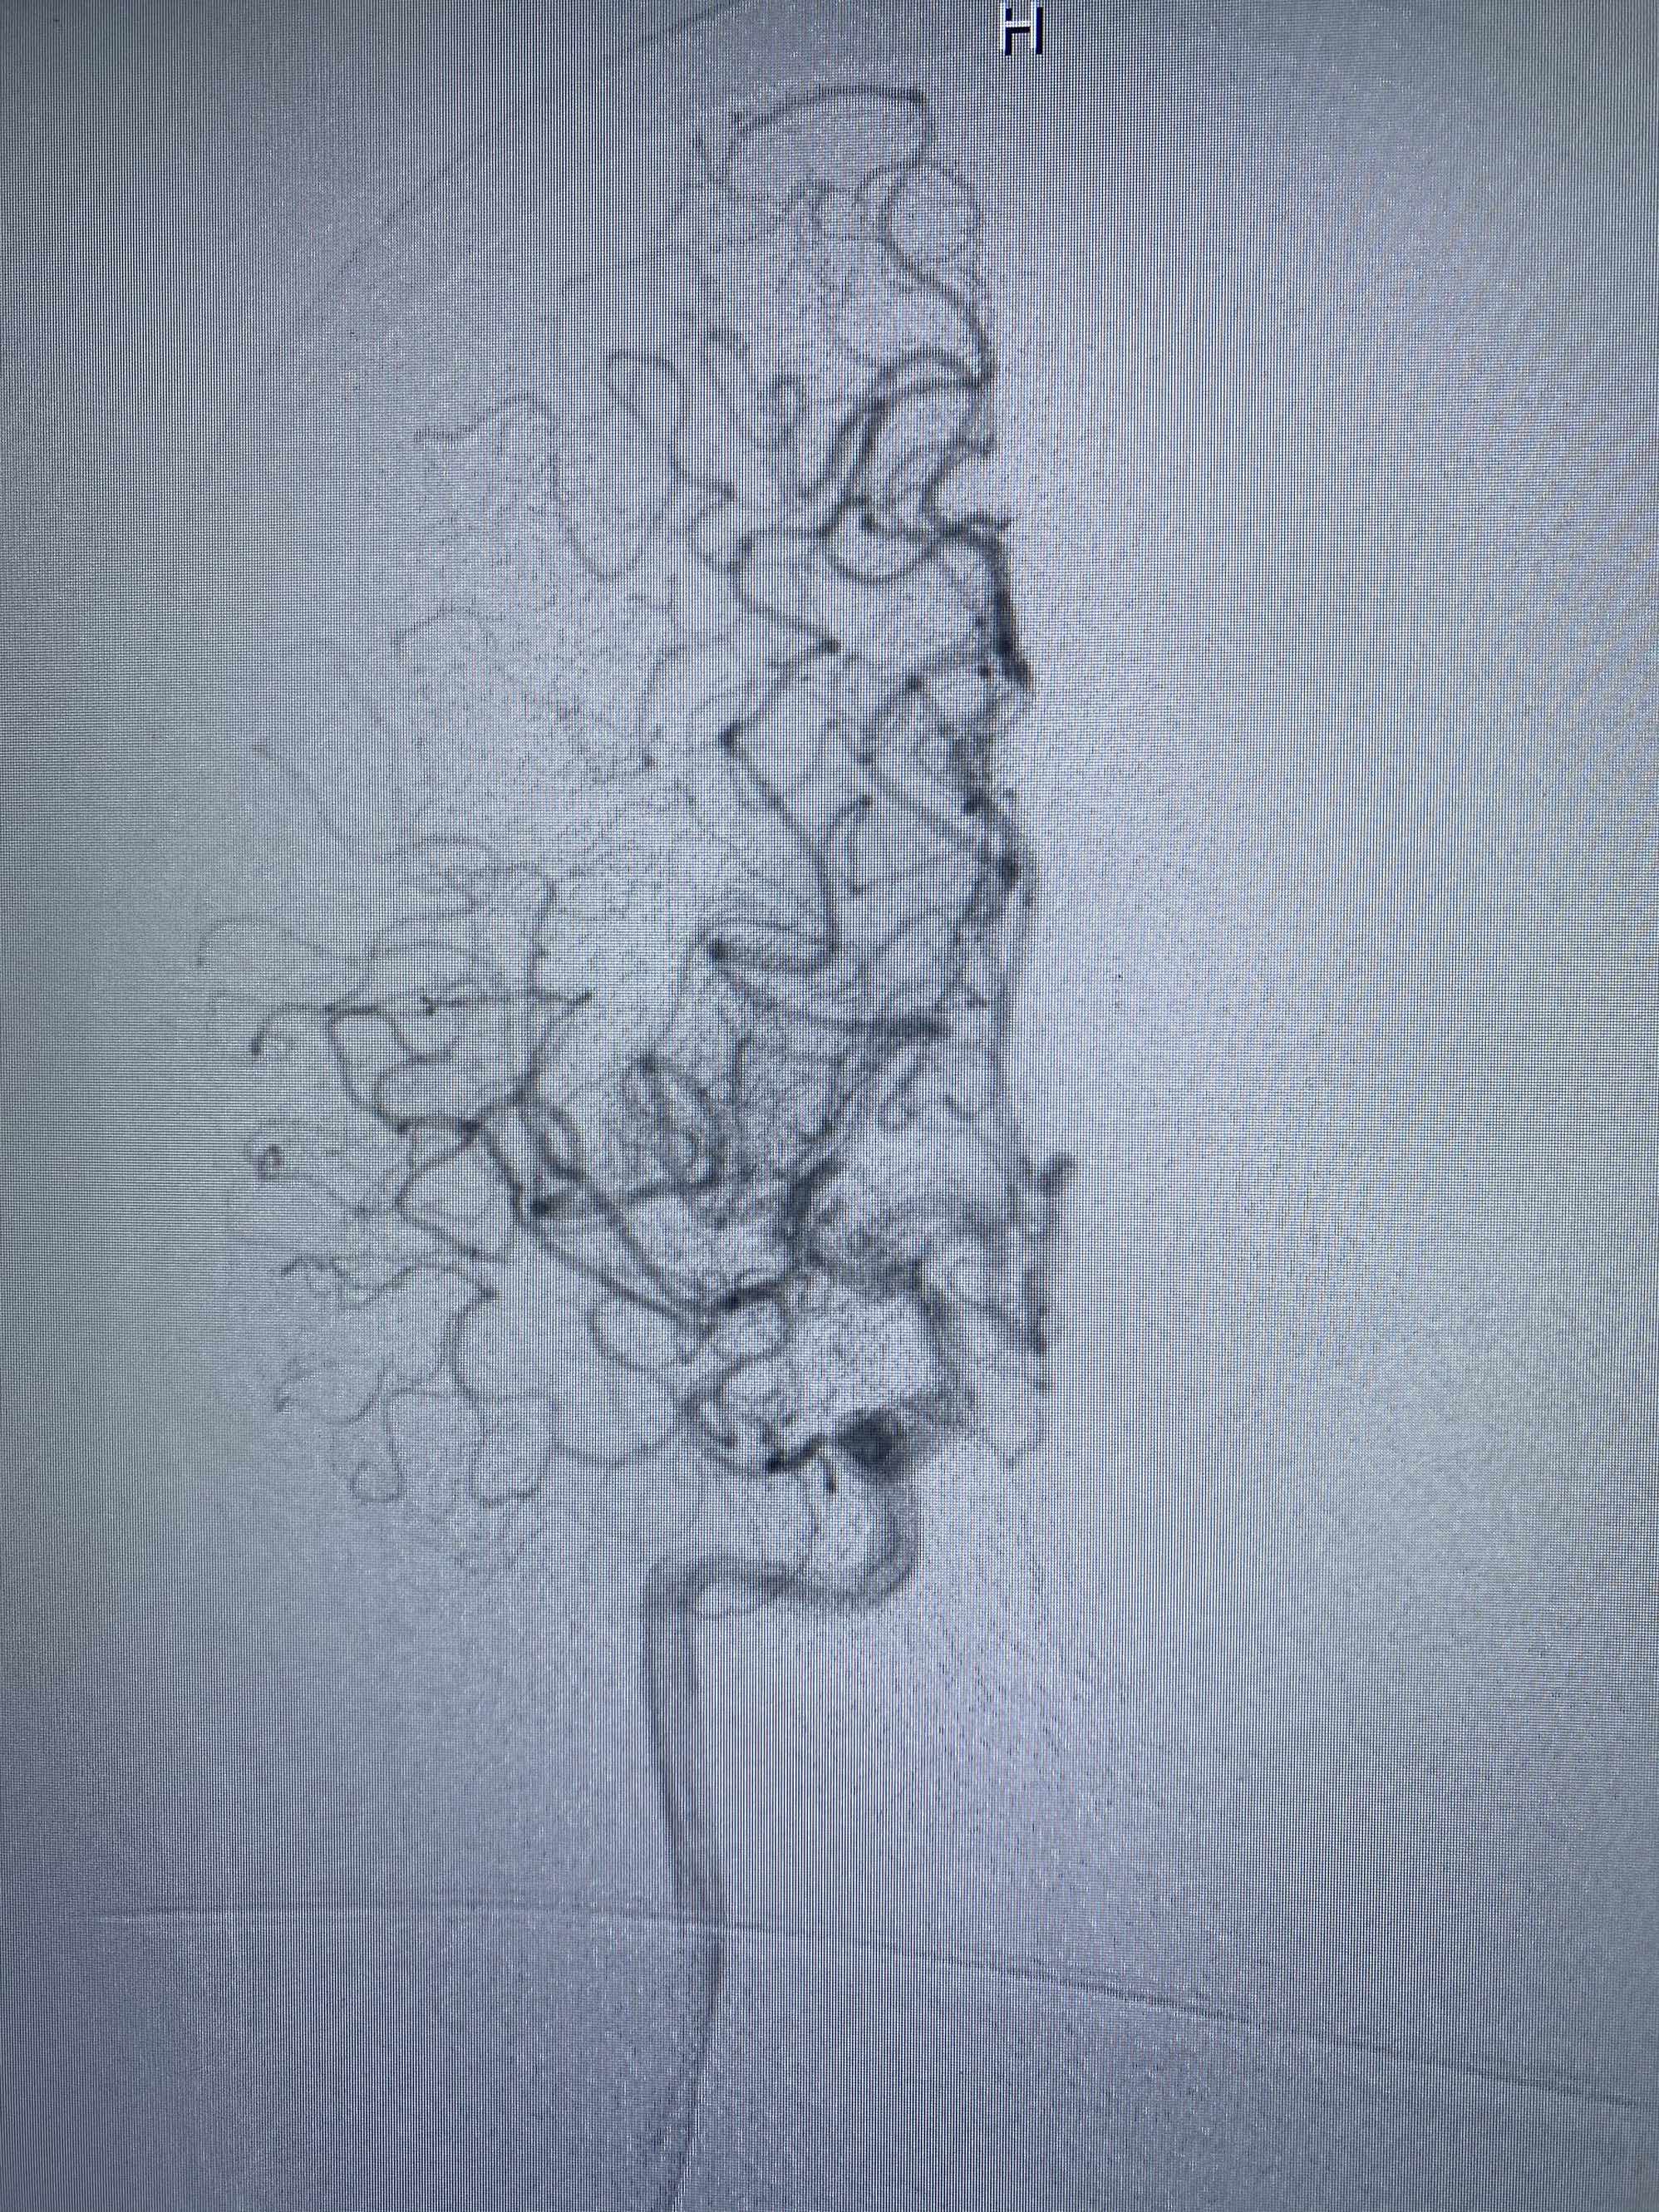

MLS,M79Y,sah,双侧MCA烟雾病,Heubner返动脉瘤,前交通段开窗,细支发出Heubner返动脉,瘤颈细长,瘤颈口比微导管细,弹簧圈2mmx3cm“隔山打牛”填塞治愈,Heubner返动脉保留。

Heubner返动脉是由大脑前动脉A1末端发出的豆纹动脉,由于走形和A1段相反,故称Heubner返动脉,该动脉梗塞可能引起尾状核头梗塞,引起偏瘫和面瘫,便身震颤等症状。